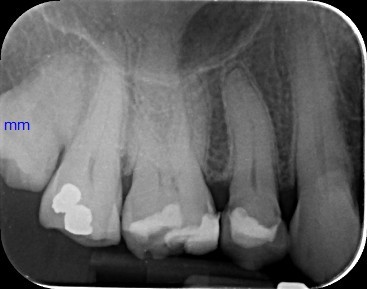

Case 1: Root Canal Treatment UR5